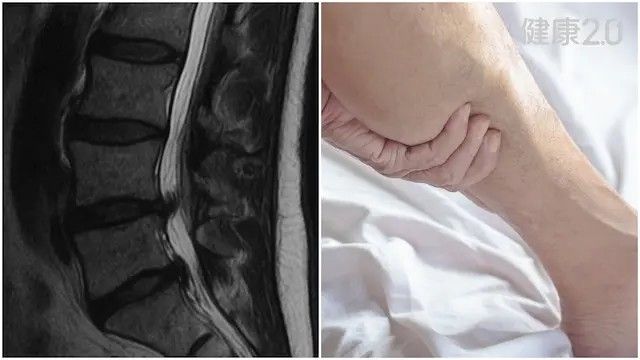

椎間盤突出是許多上班族、勞工與運動族群常見的腰背疾病之一,常因彎腰搬重物、久坐或打噴嚏後突然出現腰痛與腿麻症狀,嚴重時甚至無法行走或坐立。面對影像報告顯示的椎間盤突出,真的需要馬上手術嗎?本文帶你了解何時該開刀、中醫如何透過針刀與穴位調理達到非侵入式改善,以及日常居家自我保養的方法。

中醫師周大翔指出,椎間盤是脊椎骨間的「軟墊」,由髓核與纖維環構成,負責吸收壓力與震動。當長期姿勢不良、搬重物或椎間盤老化,內部髓核可能穿破纖維環,壓迫周圍神經,形成「椎間盤突出」。

**常見病變部位為:**L4-L5與L5-S1腰椎段。

許多患者在MRI發現椎間盤突出後,會立即擔心需要手術。但周大翔指出,研究發現,高達30%的無症狀成年人也有影像上的輕度椎間盤突出。